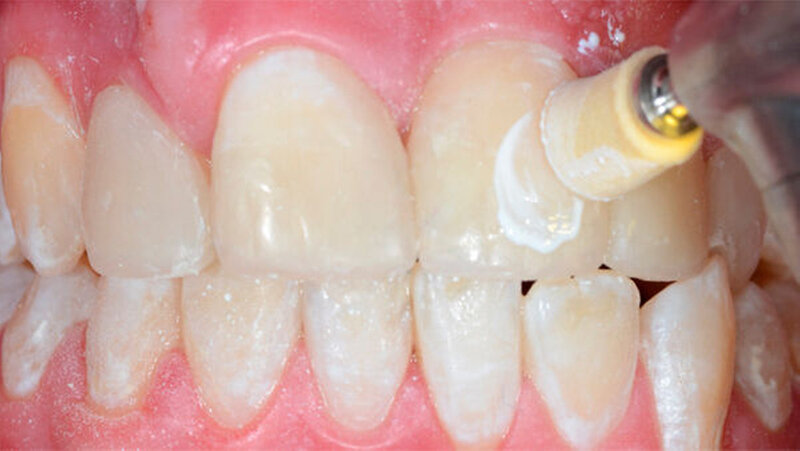

Bei diesem komplexen Fall musste mit Hilfe eines Wax-up ein Silikonschlüssel angefertigt werden, um die Formen aller Frontzähne sicher modifizieren zu können.Ceram.X Duo ermöglichte eine optimale Schichttechnik mit verschiedenen Opazitäten.

Das Alter des Patienten (17 Jahre) spielte hier eine wichtige Rolle. Der Behandlungsplan sollte möglichst keine indirekten Restaurationen beinhalten und eine eventuelle Weiterentwicklung der dentalen Situation berücksichtigen. Deshalb wurde eine minimal-invasive Lösung gewählt, und die beschriebene Schichttechnik erschien angebracht.